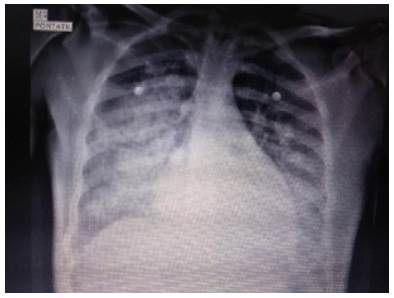

Chest x-ray showed bilateral alveolar opacities from the hilum towards the pleura in the lower two thirds of both lung fields, without images compatible with pleural effusion (Figure 1).

Regarding the lungs, oxygenation disorder was diagnosed due to gasometry findings and radiographic images compatible with acute respiratory distress syndrome (ARDS). Management with crystalloids, cathartics, activated charcoal (1 g/kg) by nasogastric tube and sodium bicarbonate infusion at 1 mEq/kg was initiated, considering acidemia secondary to intoxication.

The patient was taken to the intensive care unit where hemodynamic condition improved without requiring vasopressors; lactated ringer's crystalloid with potassium chloride 2 mEq/ hour was administered for management of mild hypokalemia. Invasive mechanical ventilation was initiated based on a diagnosis of ARDS due to radiological signs and PaO2/FiO2 ratio alteration. Possible bronchoaspiration was considered due to the compromise of the state of consciousness, which also conditioned ventilatory deterioration. She also presented difficulty in ventilatory coupling requiring neuromuscular block and deep sedation.